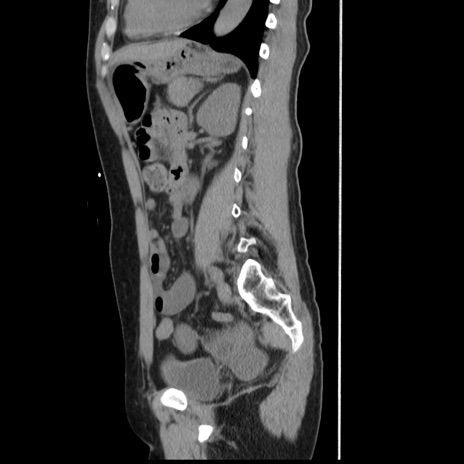

冠状断像